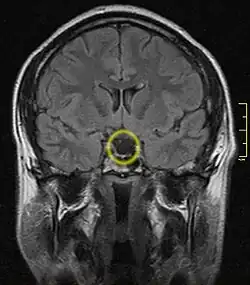

| Empty sella turcica on MRI as seen in severe cases of Sheehan's syndrome | |

MRI is useful in diagnosing Sheehan's syndrome since it examines the structure of the pituitary and may identify any anatomical damage.[5] MRI findings will vary based on how early or late in the disease process the test is being conducted. If an MRI is conducted early enough in the disease process the pituitary may appear larger than normal, and show changes that are consistent with damage from lack of blood supply.[16] Later in the disease process of this syndrome the damage imposed on the pituitary gland will cause it to shrink, and leave a partially empty or totally empty sella turcica on MRI.[8]